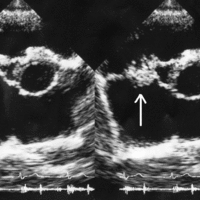

Bacterial endocarditis is an infection of the inner surface of the heart or heart valves caused by the presence of bacteria in the blood.